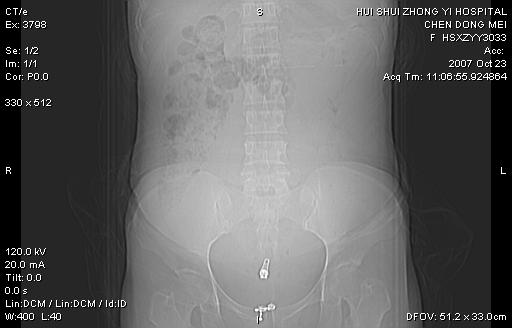

标题: CT10156:女.43岁,发现中下腹部包都块2年 [打印本页]

发现中下腹部包都块2年。2年来月经不规律。

腹腔巨大软组织密度影,边缘光滑,包膜完整,内囊变坏死。腹膜后及盆腔内淋巴结肿大。结合病史考虑卵巢癌可能性大。

病变巨大,呈囊实性改变,包膜较厚且完整,内见分膈,周围脏器明显受压移位,病变与左侧附件关系密切,考虑来源左侧附件的囊腺瘤,不除外癌变可能;畸胎瘤可能性较小。

病变巨大,呈囊实性改变,包膜较厚且完整,内见分膈,周围脏器明显受压移位,病变与左侧附件关系密切,考虑来源左侧附件的囊腺瘤,盆腔内见肿大淋巴结,不除外癌变可能。

病变巨大,呈囊实性改变,包膜较厚且完整,内见分膈,周围脏器明显受压移位,病变与左侧附件关系密切,考虑来源左侧附件的囊腺瘤,不除外癌变可能